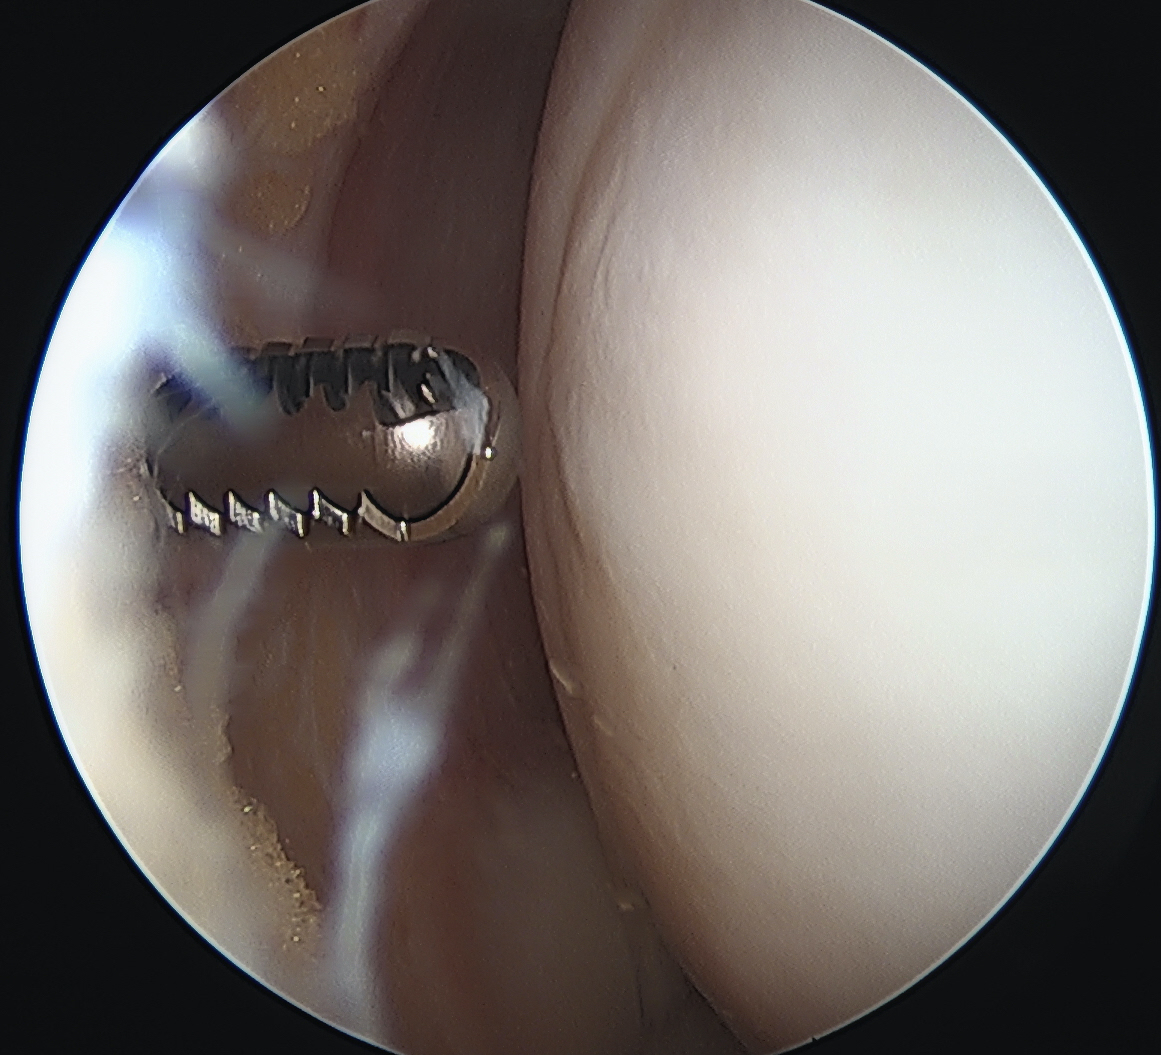

- ensure screw heads are buried under cartilage, but not too deep so they still engage fragment

- can microfracture with 1 mm k wire around screws

- ensure K wires centered in fragment

- flex and extend knee to place inferior / superior screws

- typically 2 - 3 screws maximum (3.5 mm)

- can microfracture around screws

Inferior screw Superior screw